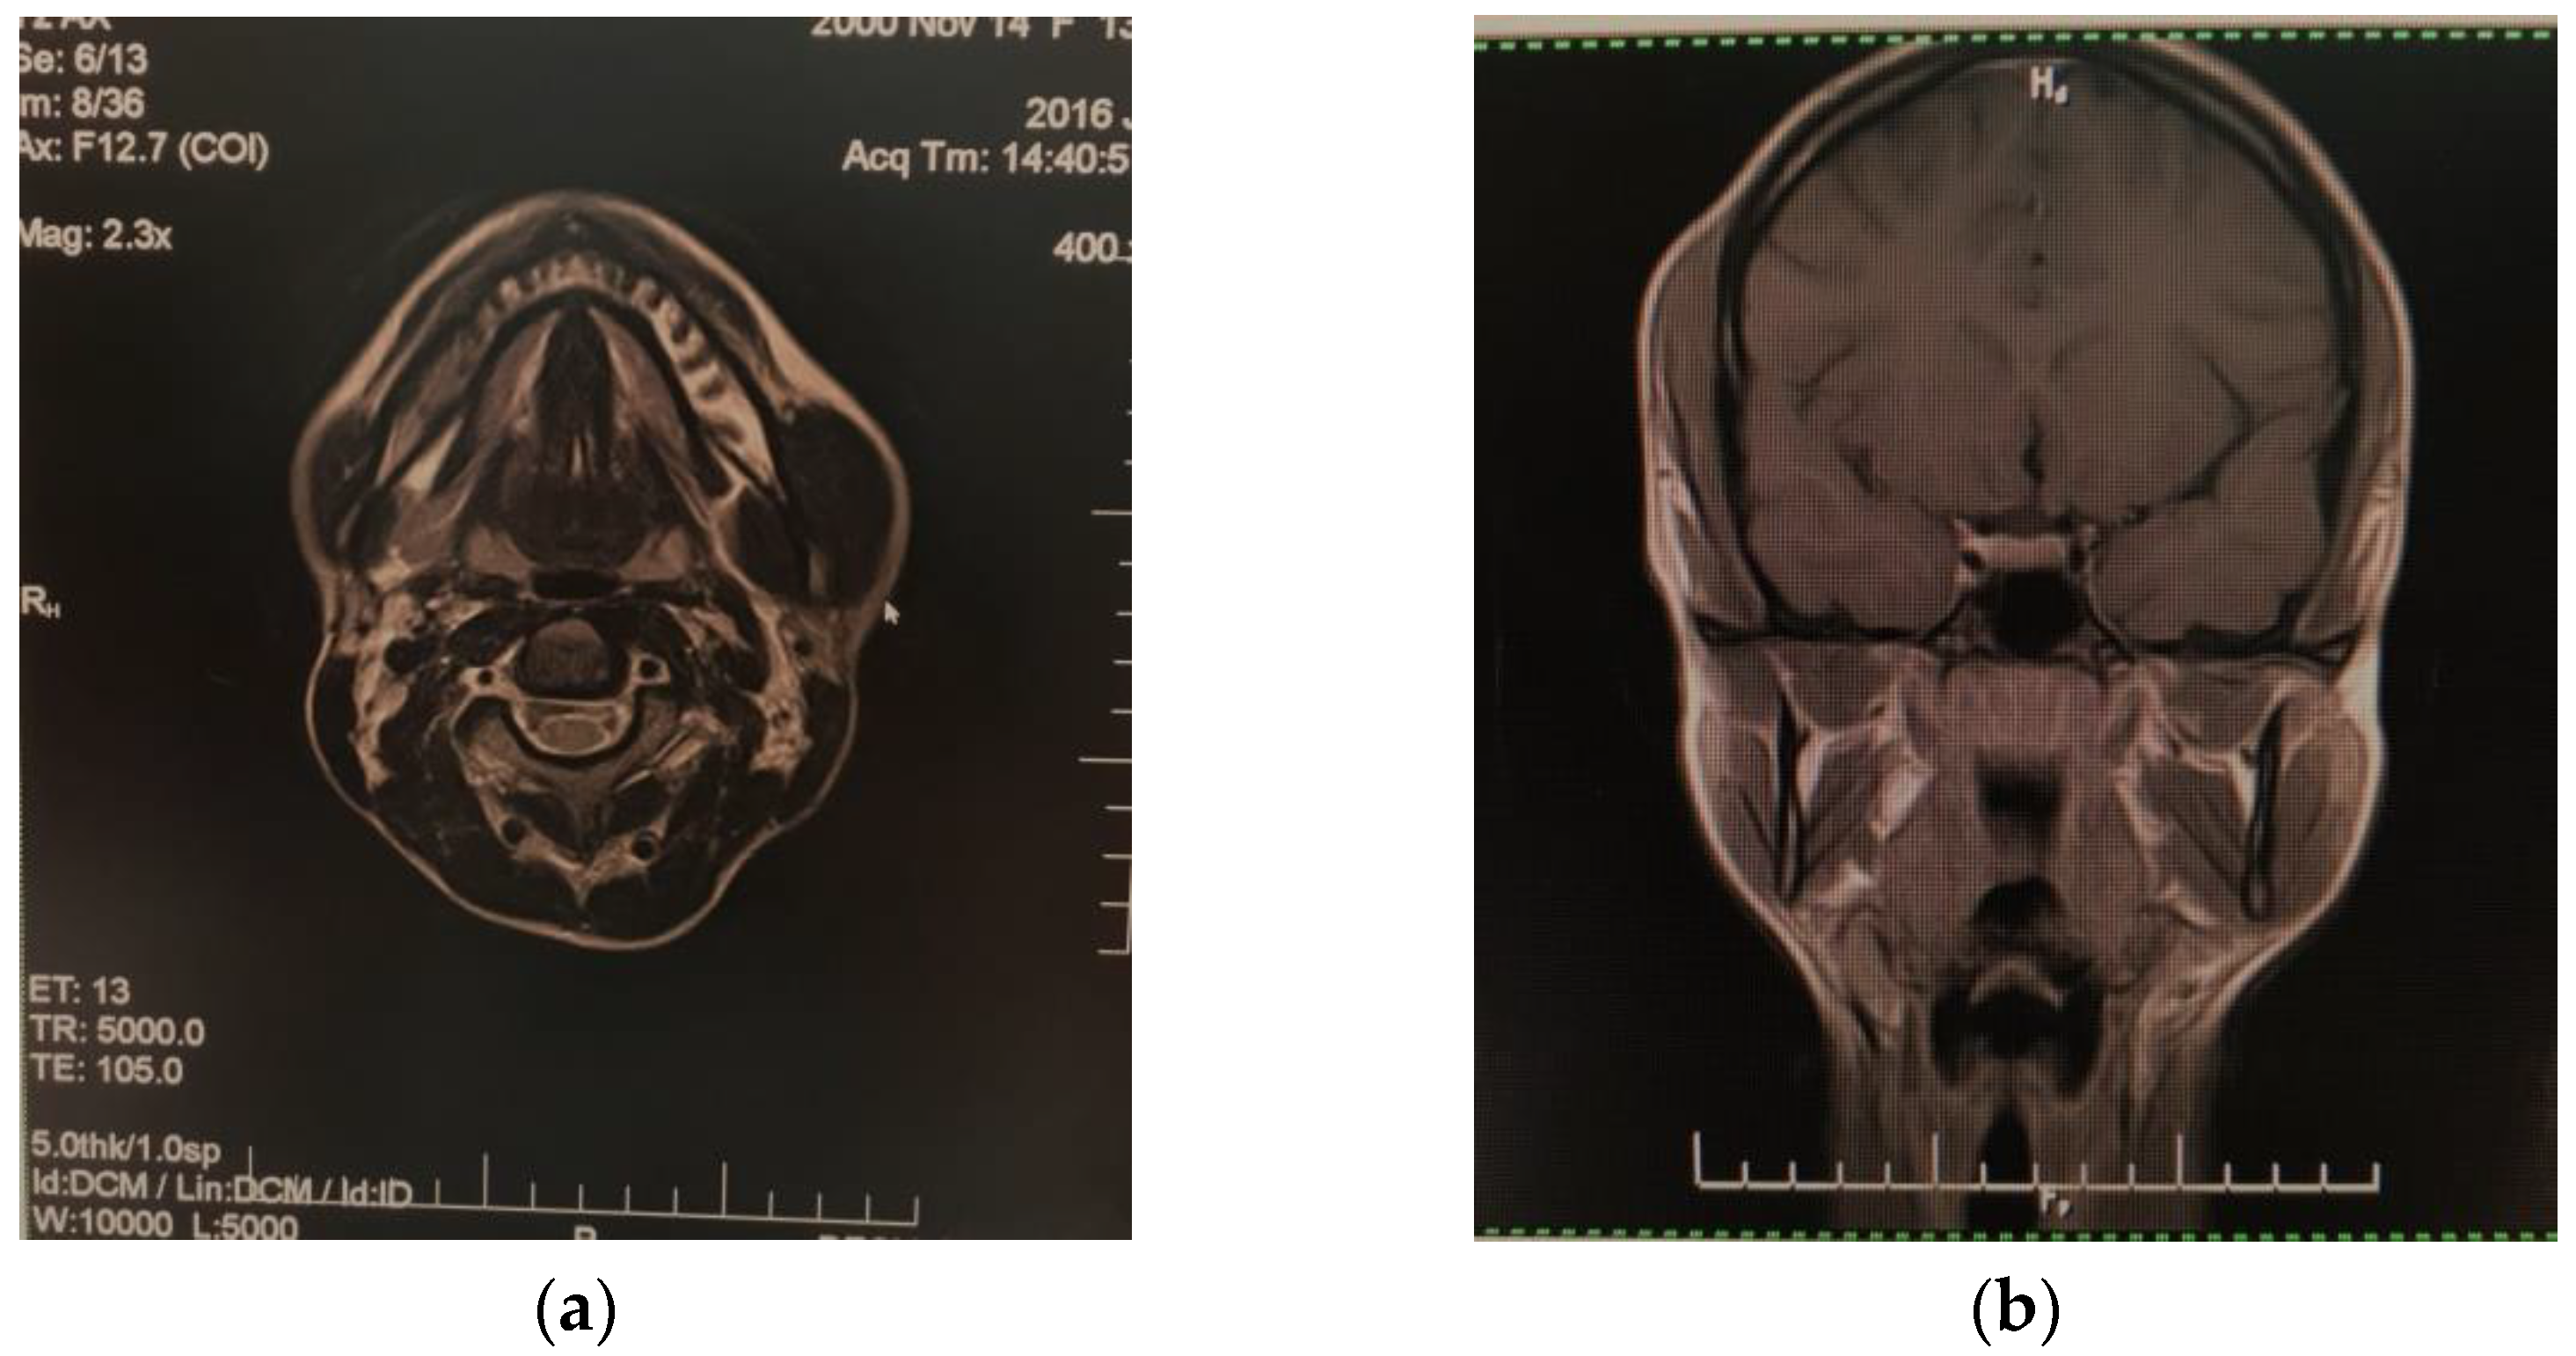

Anamnesis revealed that she chewed on both sides, did not generally use chewing gum that there was no history of face injury, dental conditions, mental disorders, or parafunctional activities such as bruxism. No local inflammatory phenomena were detected and the consistency of the area was normal, homogeneous, painless, and with no signs of abnormalities due to dental occlusion. The initial differential diagnosis included a condition of the salivary glands, a lymphatic or arteriovenous malformation, a muscle tumor, or lipoma. All these conditions were ruled out with the help of clinical multidisciplinary investigations (psychological, neurosurgical, dentoalveolar and maxillofacial surgery, and ophthalmological consultation), biological tests, and medical imaging scanning (the findings were within the reference range). The ultrasound scanning of the masseter area revealed hypertrophied muscle tissue measuring 13/48 mm. Nuclear magnetic resonance (NMR) suggested the diagnosis of hypertrophy of the left masseter muscle as it was double in size compared to the contralateral muscle; muscle morphology and signal strength were normal, with no significantly high contrast agent uptake on the impaired side compared to the normal side (Figure 2). No other intracranial abnormalities or bone damage in the mandible were identified.

Figure 2. Nuclear magnetic resonance aspect of left masseter hypertrophy: (a) cross-plane; (b) coronal plane.

The diagnosis may be clinical, by palpating the masseter muscle with fingers while the patient clenches his/her teeth so the muscle is more prominent during contraction [10]. The masseter muscles are most typically injured, they are variably enlarged and they can be up to three times the size of the contralateral muscles. At imaging, they are normal in appearance without increased contrast [13]; periosteal appositions may occur and be visible on the lower branch of the mandible on the affected side, yet these were not detected in the case reported here. Early diagnosis of masseteric hypertrophy is important so that the patient and parents can be informed about the likely development of facial asymmetry.